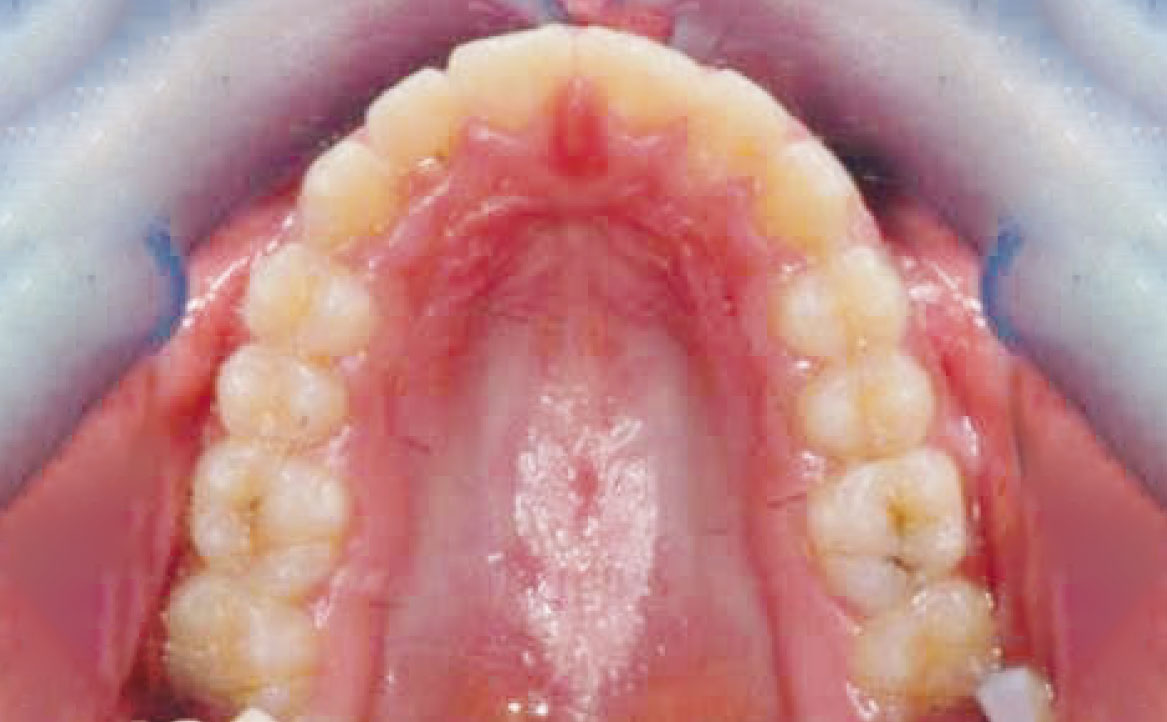

I risultati ottenuti sono mostrati nelle figure da 20 a 27.

La prima fase di trattamento ha previsto l’applicazione di un espansore palatale per dodici mesi. Tale dispositivo, applicando una pressione controllata sulla regione palatale, ha permesso di ottenere l’espansione dell’arcata superiore. Questa prima fase terapeutica ha consentito di preparare l’arcata superiore ad accogliere l’arcata inferiore durante la correzione ortopedica della retrusione mandibolare e della micro-mandibolia mediante Twin Block.

La terza fase, ossia quella eseguita mediante l’apparecchiatura ortodontica fissa, ha consentito di ottenere un buon allineamento dentario e affinare l’intercuspidazione tra l’arcata superiore e inferiore.

Il trattamento ha permesso di ottenere corretti rapporti trasversali tra i mascellari, un buon allineamento delle linee mediane e una corretta posizione dei denti, con conseguente riduzione dell’esposizione gengivale.